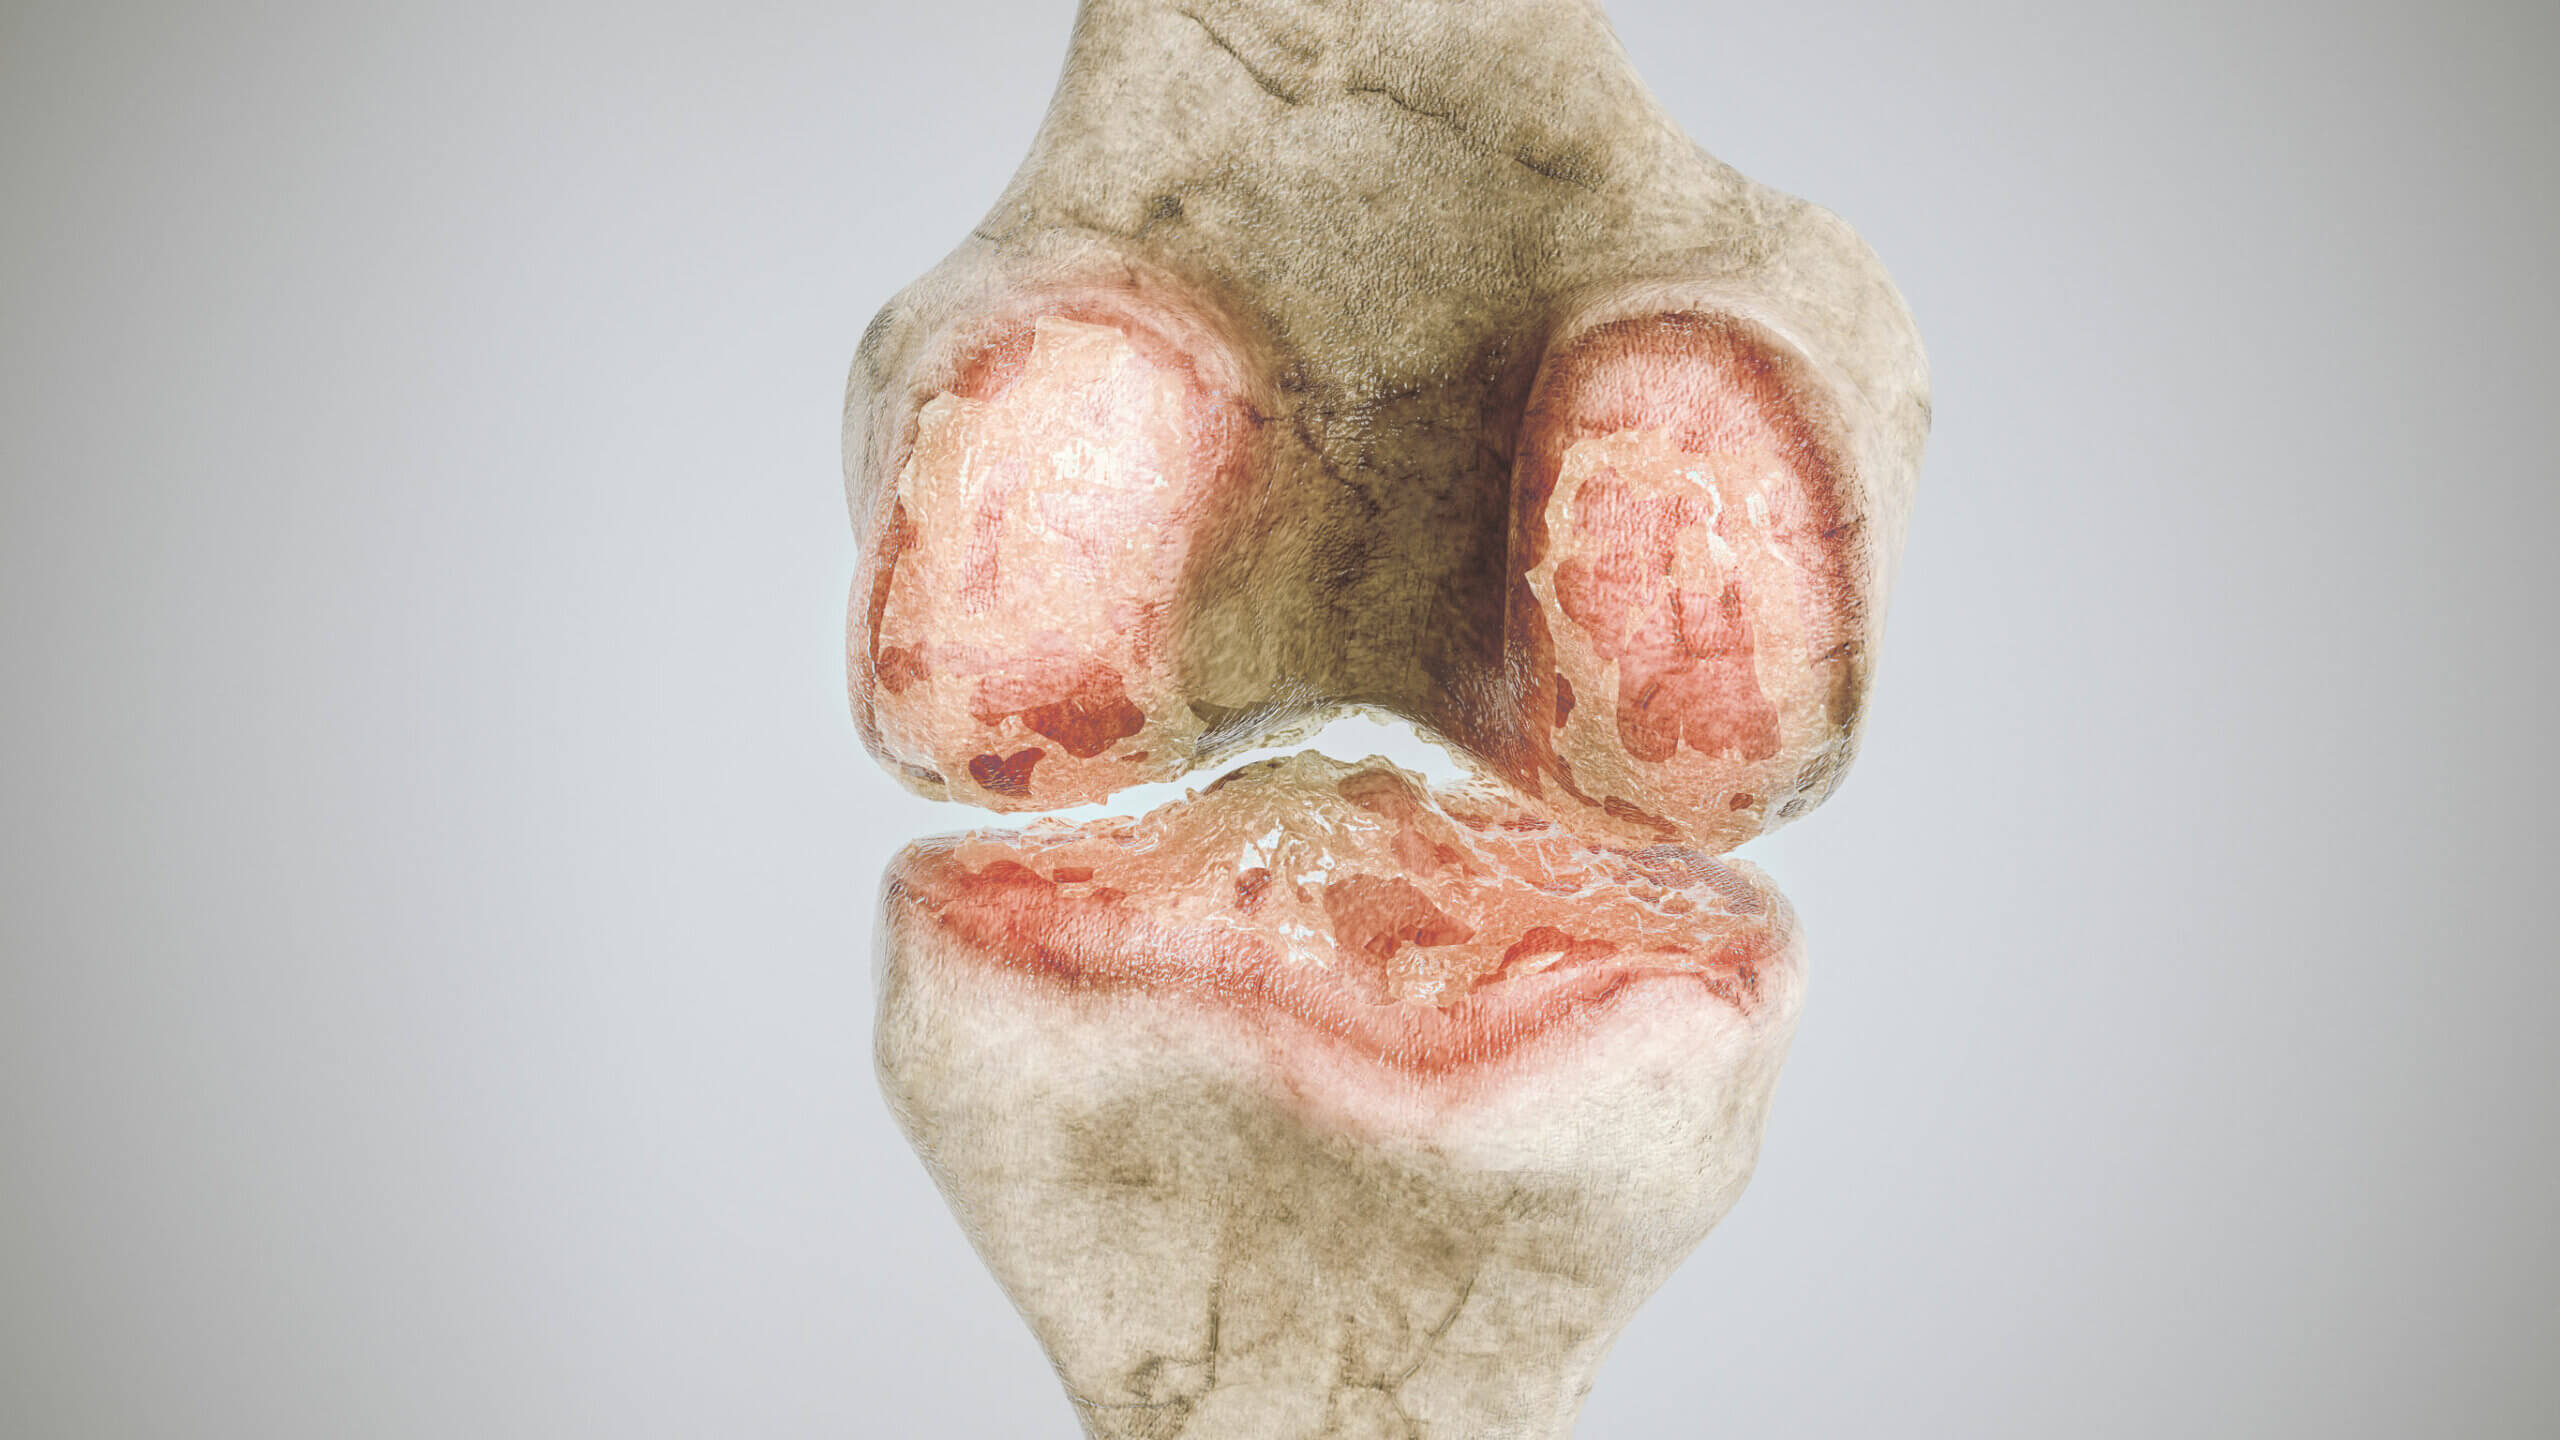

Artrose

Artrose is een degeneratieve aandoening van de gewrichten, waarvan de incidentie aanzienlijk toeneemt met de leeftijd. Het kan een groot aantal gewrichten aantasten, ongeacht de grootte. Vanuit klinisch oogpunt is gewrichtspijn het meest opvallende aspect. Dit kan gepaard gaan met stijfheid en af en toe een verdikking.

Op radiologisch niveau is het mogelijk om enkele structuren te laten zien die osteofyten (Engelse link) worden genoemd, benige uitsteeksels die zich gewoonlijk aan de uiteinden van de botten ontwikkelen.